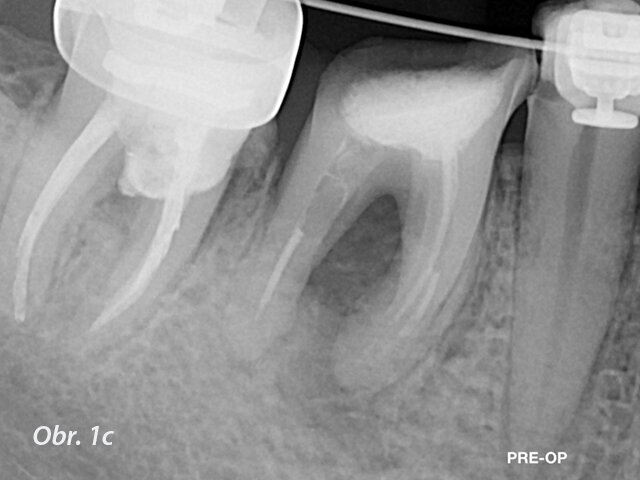

I při opracování kanálků se samozřejmě lze dopustit mnoha chyb, jako je například via falsa, perforace nebo transportace kanálku, oddělení nástroje a další. Jedna z nejvíce stresujících věcí pro ošetřujícího je perforace kanálku. Perforace v kanálku může vzniknout kvůli špatné sekvenci nástrojů, kvůli obecně špatné technice nebo kvůli technice s nadměrným třením. Pak se perforace může objevit na vnitřní straně ohybu kanálku. Když se to stane, často se setkáme s výrazným krvácením a problémy s viditelností. Situace se ještě více zkomplikuje, když se začneme zabývat staršími perforacemi spojenými s lézemi (obr. 1a–c).